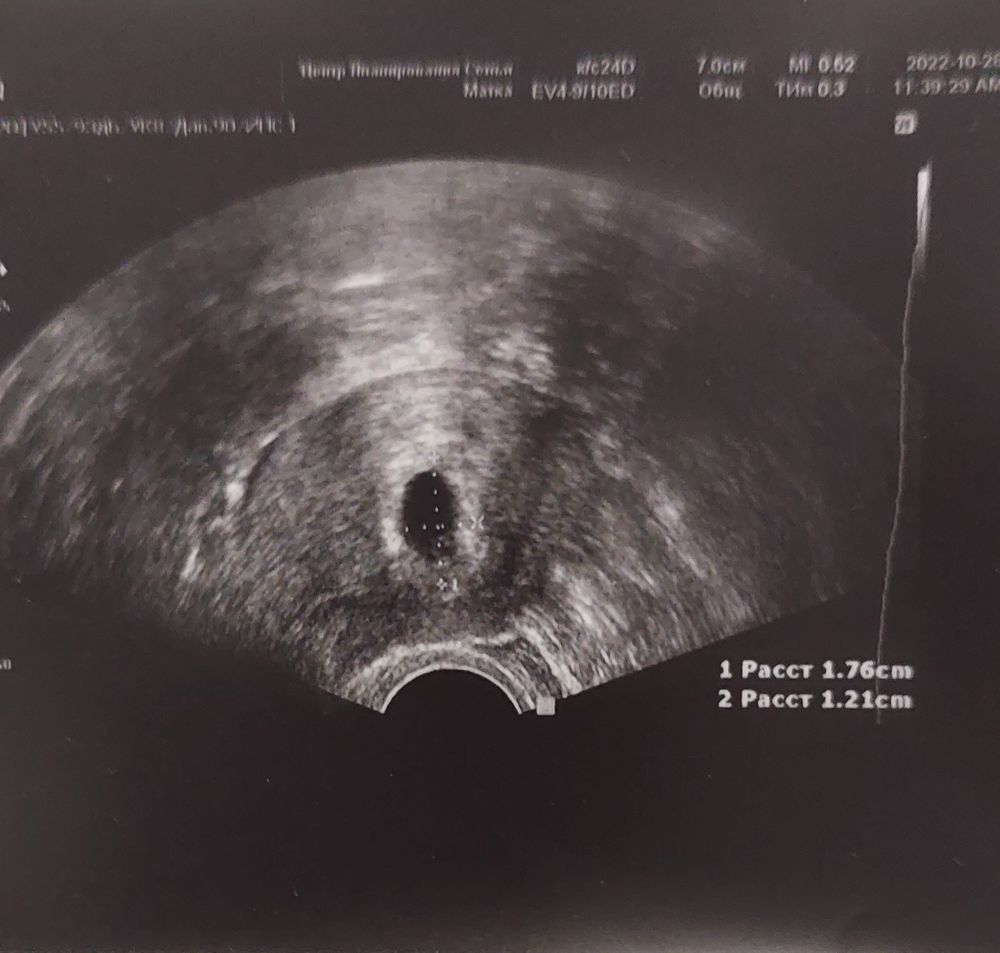

Итак, спустя пять дней переживаний, я таки дождалась узи. И все ок👻 ни отслоек ни тонуса не увидели, зато увидели пя с тем самым мешочком 🤗 я была приятно удивлена. Ре Сказала, что кровит из-за скочка гормонов. Назначила уколы прогестерона вм. Уколы ставить боюсь, муж не поможет тк в командировке, решила купить спасилен (аппарат для инъекций) завтра попробую. Следующее узи через 2 недели. До тех пор максимум лежать и тяжелее ложки не поднимать ничего 😶 но я решила продолжать работать, сократив количество клиентов до трех в день. Отдых между клиентами не менее часа, сам массаж не более полутора часов. Если будет плохо, естественно отменяю эту затею. (но деньги капец как нужны с этими прогиновами и платными приёмами, ещё и хранение двух оставшихся эмбрионов)